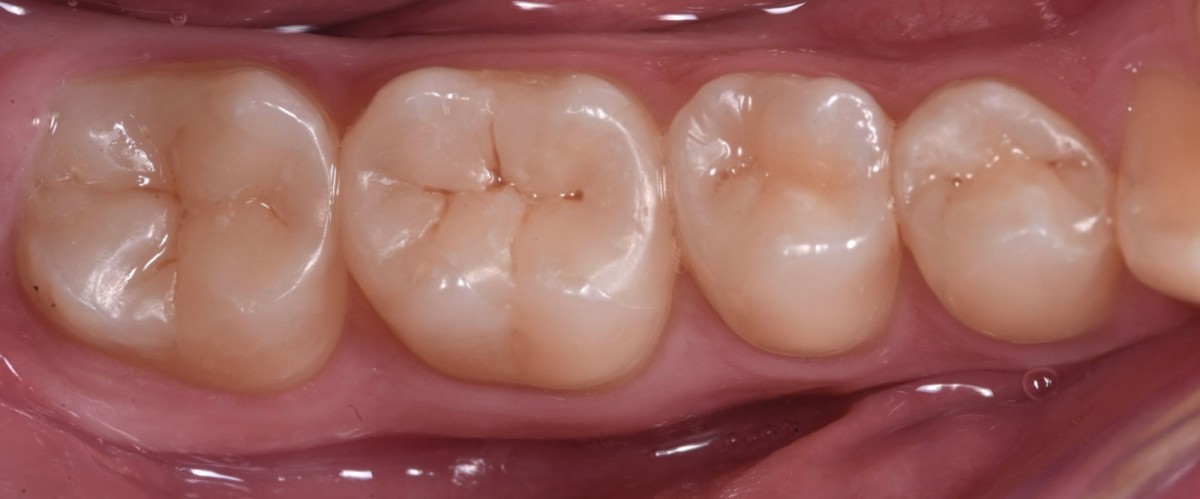

A 24-year-old male patient came to my attention reporting sensibility related to sweet and cold on the 3rd quadrant. The general medical history revealed nothing relevant.

Clinical examination highlighted old direct restorations on 3.7 and 3.6, with irregular margins and initial signs of infiltration. Rx examination (orthopantomography and bitewings) revealed primary interproximal decays with dentinal involvement on 3.4, 3.5, 3.6 and 3.7. Vitality test was carried out and confirmed that all elements were vital.

According to the fact that the patient was young and all the teeth had a sufficient quantity of sound tissue structure, a minimally invasive approach with direct restorations was proposed.

Oral hygiene motivation was carried out, alongside with proper periodontal treatment (scaling, polishing) before taking initial photo (Fig.1). Initial rx bitewing of the quadrant (Fig.2).